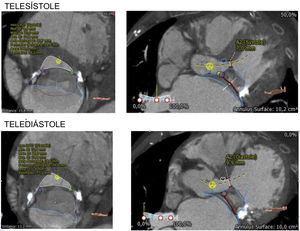

El TC sincronizado multifase nos confirma la idoneidad del paciente para el implante de TMVR (fig. 3). Se cuantifica el perímetro y área del anillo mitral, el diámetro septo-lateral, intercomisural e intertrígono, las dimensiones del ventrículo izquierdo, el ángulo aorto-mitral, la calcificación del anillo mitral y el flujo de salida del ventrículo izquierdo. Un neo-TSVI mayor a 250mm2 es el valor predicho aceptado para evitar una obstrucción del TSVI hemodinámicamente relevante tras el implante15. Mediante la evaluación de las dimensiones previas, se determina el tamaño protésico, punto de acceso y ángulos de implante. Todo ello tiene como objetivo disminuir la incidencia de leak periprotésico y de obstrucción del tracto de salida del ventrículo izquierdo postoperatorio, y facilitar un implante exitoso de la prótesis16–18.